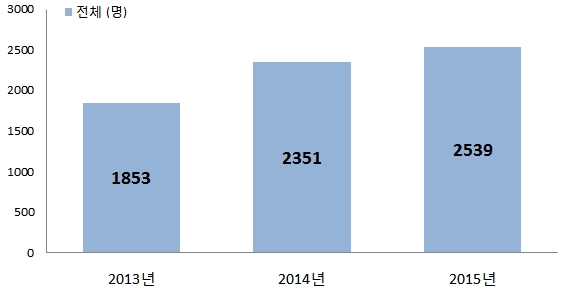

대부분 충치 치료를 받은 치아는 다시 충치가 생기지 않을 것이라 생각하지만 결코 그렇지 않다. 일산사과나무치과병원에서 치료한 치아에 충치가 생겨 다시 병원을 찾은 내원 환자 수를 조사한 결과 2013년 전체 내원 환자 수 1,853명에서 2014년 2,351명, 2015년 2,539명으로 증가한 것으로 나타났다. 이처럼 환자 수가 증가한 이유는 스케일링 건강 보험이 적용되면서 치과를 방문하는 사람들이 많아졌고, 구강 건강에 대한 관심이 높아지면서 정기 검진을 받는 사람들이 많기 때문으로 분석되고 있다.